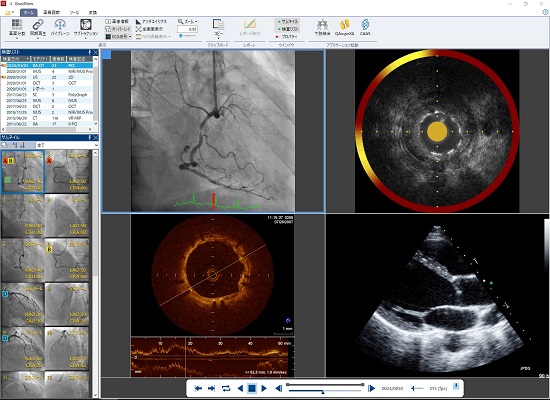

Goodnetは販売開始から今年で20周年という節目を迎え、Ver.6からVer.7へと大きな進化を遂げた。Ver.7では、主に循環器分野

で発生するDICOM画像の保存・配信はもちろん各種検査レポートの作成から画像解析、さらには管理が煩雑になりがちな非DICOM

ファイルも一元管理を可能にすることで、これまで以上に幅広く柔軟に医療現場をサポートするCardiology総合管理ソリューショ

ンとなっている。